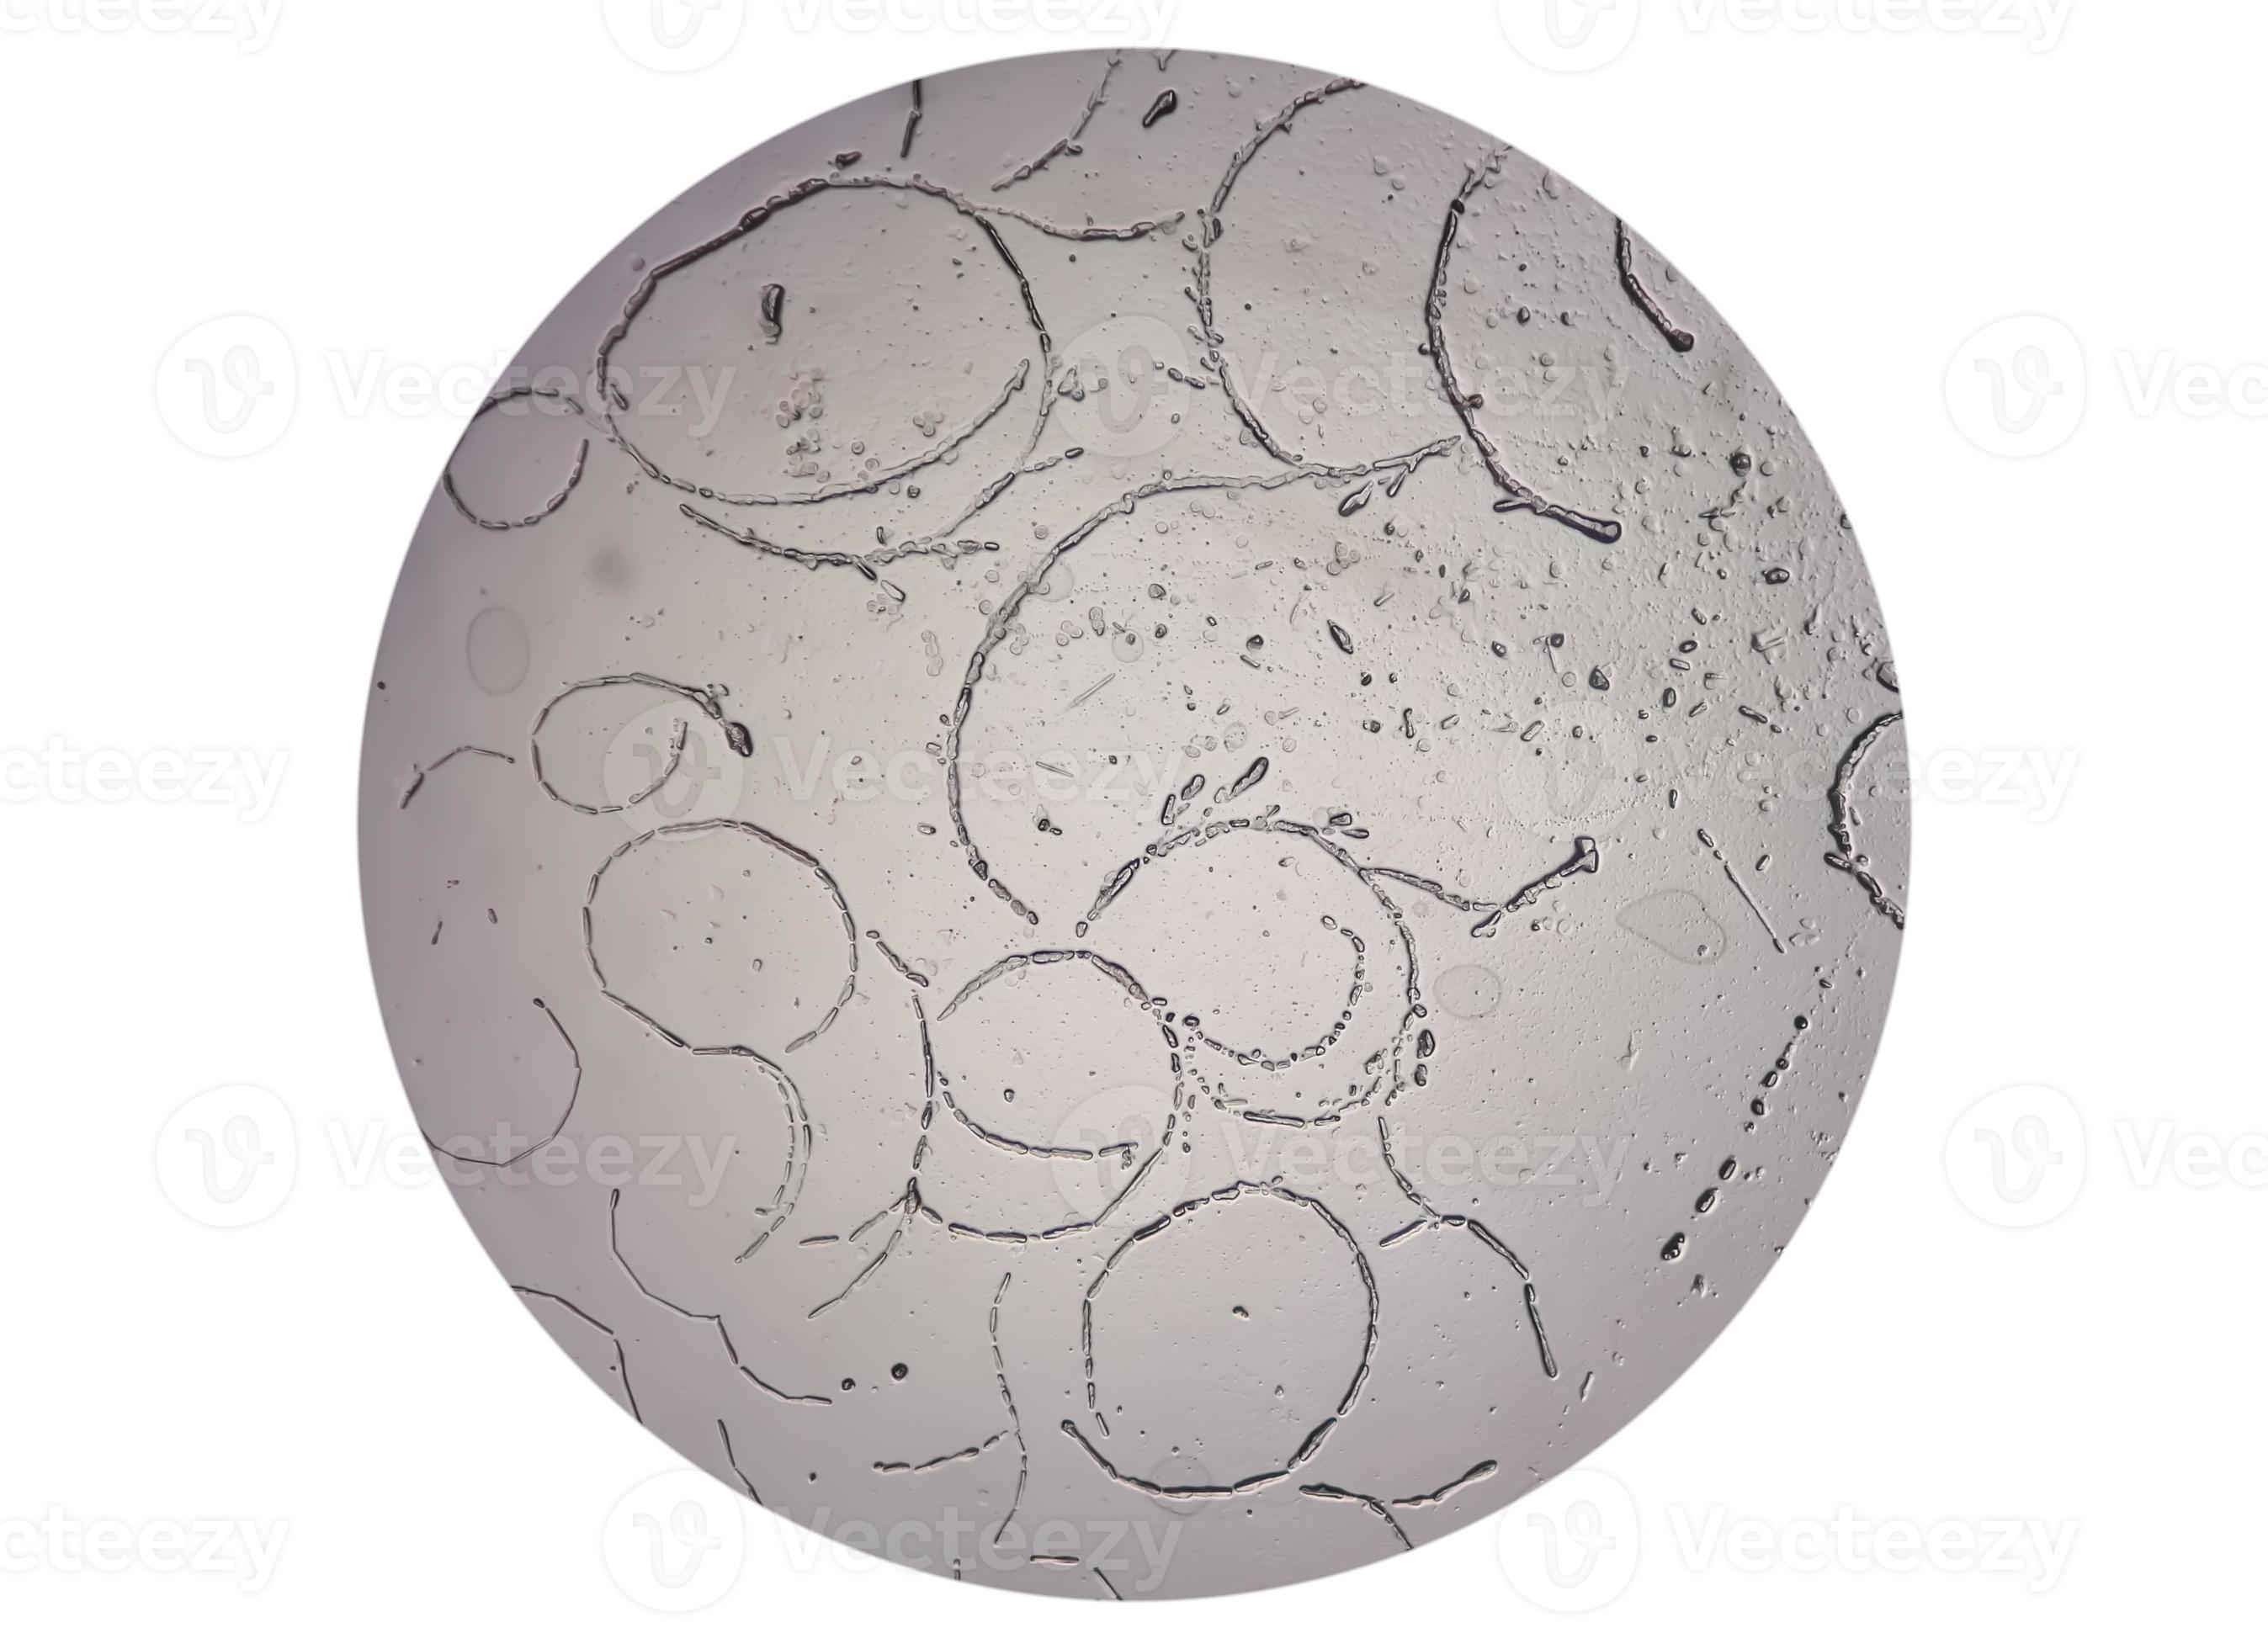

From www.vecteezy.com

Microscopic image showing Hyphae of dermatophytes,, skin scraping for Skin Scraping Test For Eczema Learn how your doctor can diagnose eczema based on your skin exam, medical history, and possible tests. Screening tests for food allergy include skin prick test and specific ige blood test. It is characterized by pruritus, scratching, and eczematouslesions (dry, scaling and crusted areas of skin), and when chronic. National skin centre offers a comprehensive range of laboratory tests for. Skin Scraping Test For Eczema.